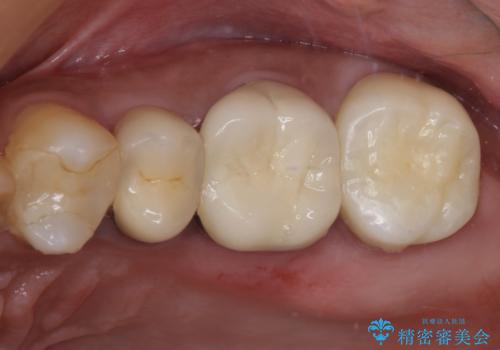

食事で痛む 神経を極力残した虫歯治療